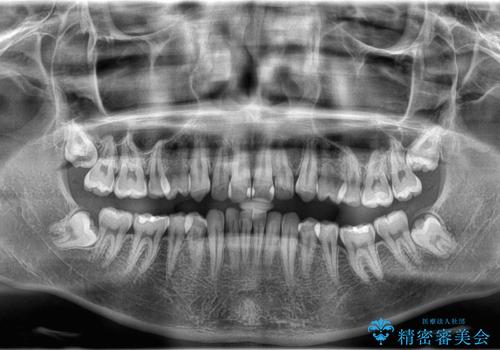

- 咬み合わせの不調和と歯並びのデコボコを主訴にご来院された患者様です。

精密矯正検査の結果、歯を抜かずに非抜歯でワイヤー矯正で治療を行う方針としました。

叢生(歯のデコボコ)の量が多く、加えてディープバイト(過蓋咬合)や重度の捻転も認められたため、リンガルアーチやマイクロインプラントなどの補助装置を併用し、治療を進めました。

治療途中では咬み合わせの改善を目的としてバイトアップを行い、歯の捻転や叢生を改善しつつ、機能的に安定した咬合を獲得しています。

治療期間は3年2ヵ月と比較的長期となりましたが、見た目の歯並びだけでなく、咬み合わせまでしっかり整えた症例です。

上顎左右4番は90度捻転していたため、改善後歯根露出してしまっているためCTG(歯肉移植)を行う予定です。